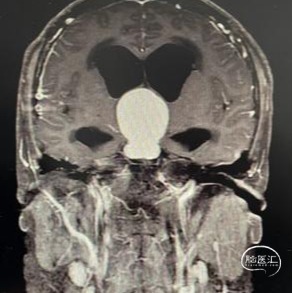

头部MRI显示:鞍区-鞍上区-第三脑室可见一不规则囊状长T1极长T2信号灶,大小约43mm*32mm*43mm,增强后可见病灶不均匀明显强化。垂体及视交叉未见显示,双侧脑室扩张,双侧脑室旁可见对称性斑片状长T1长T2信号灶。